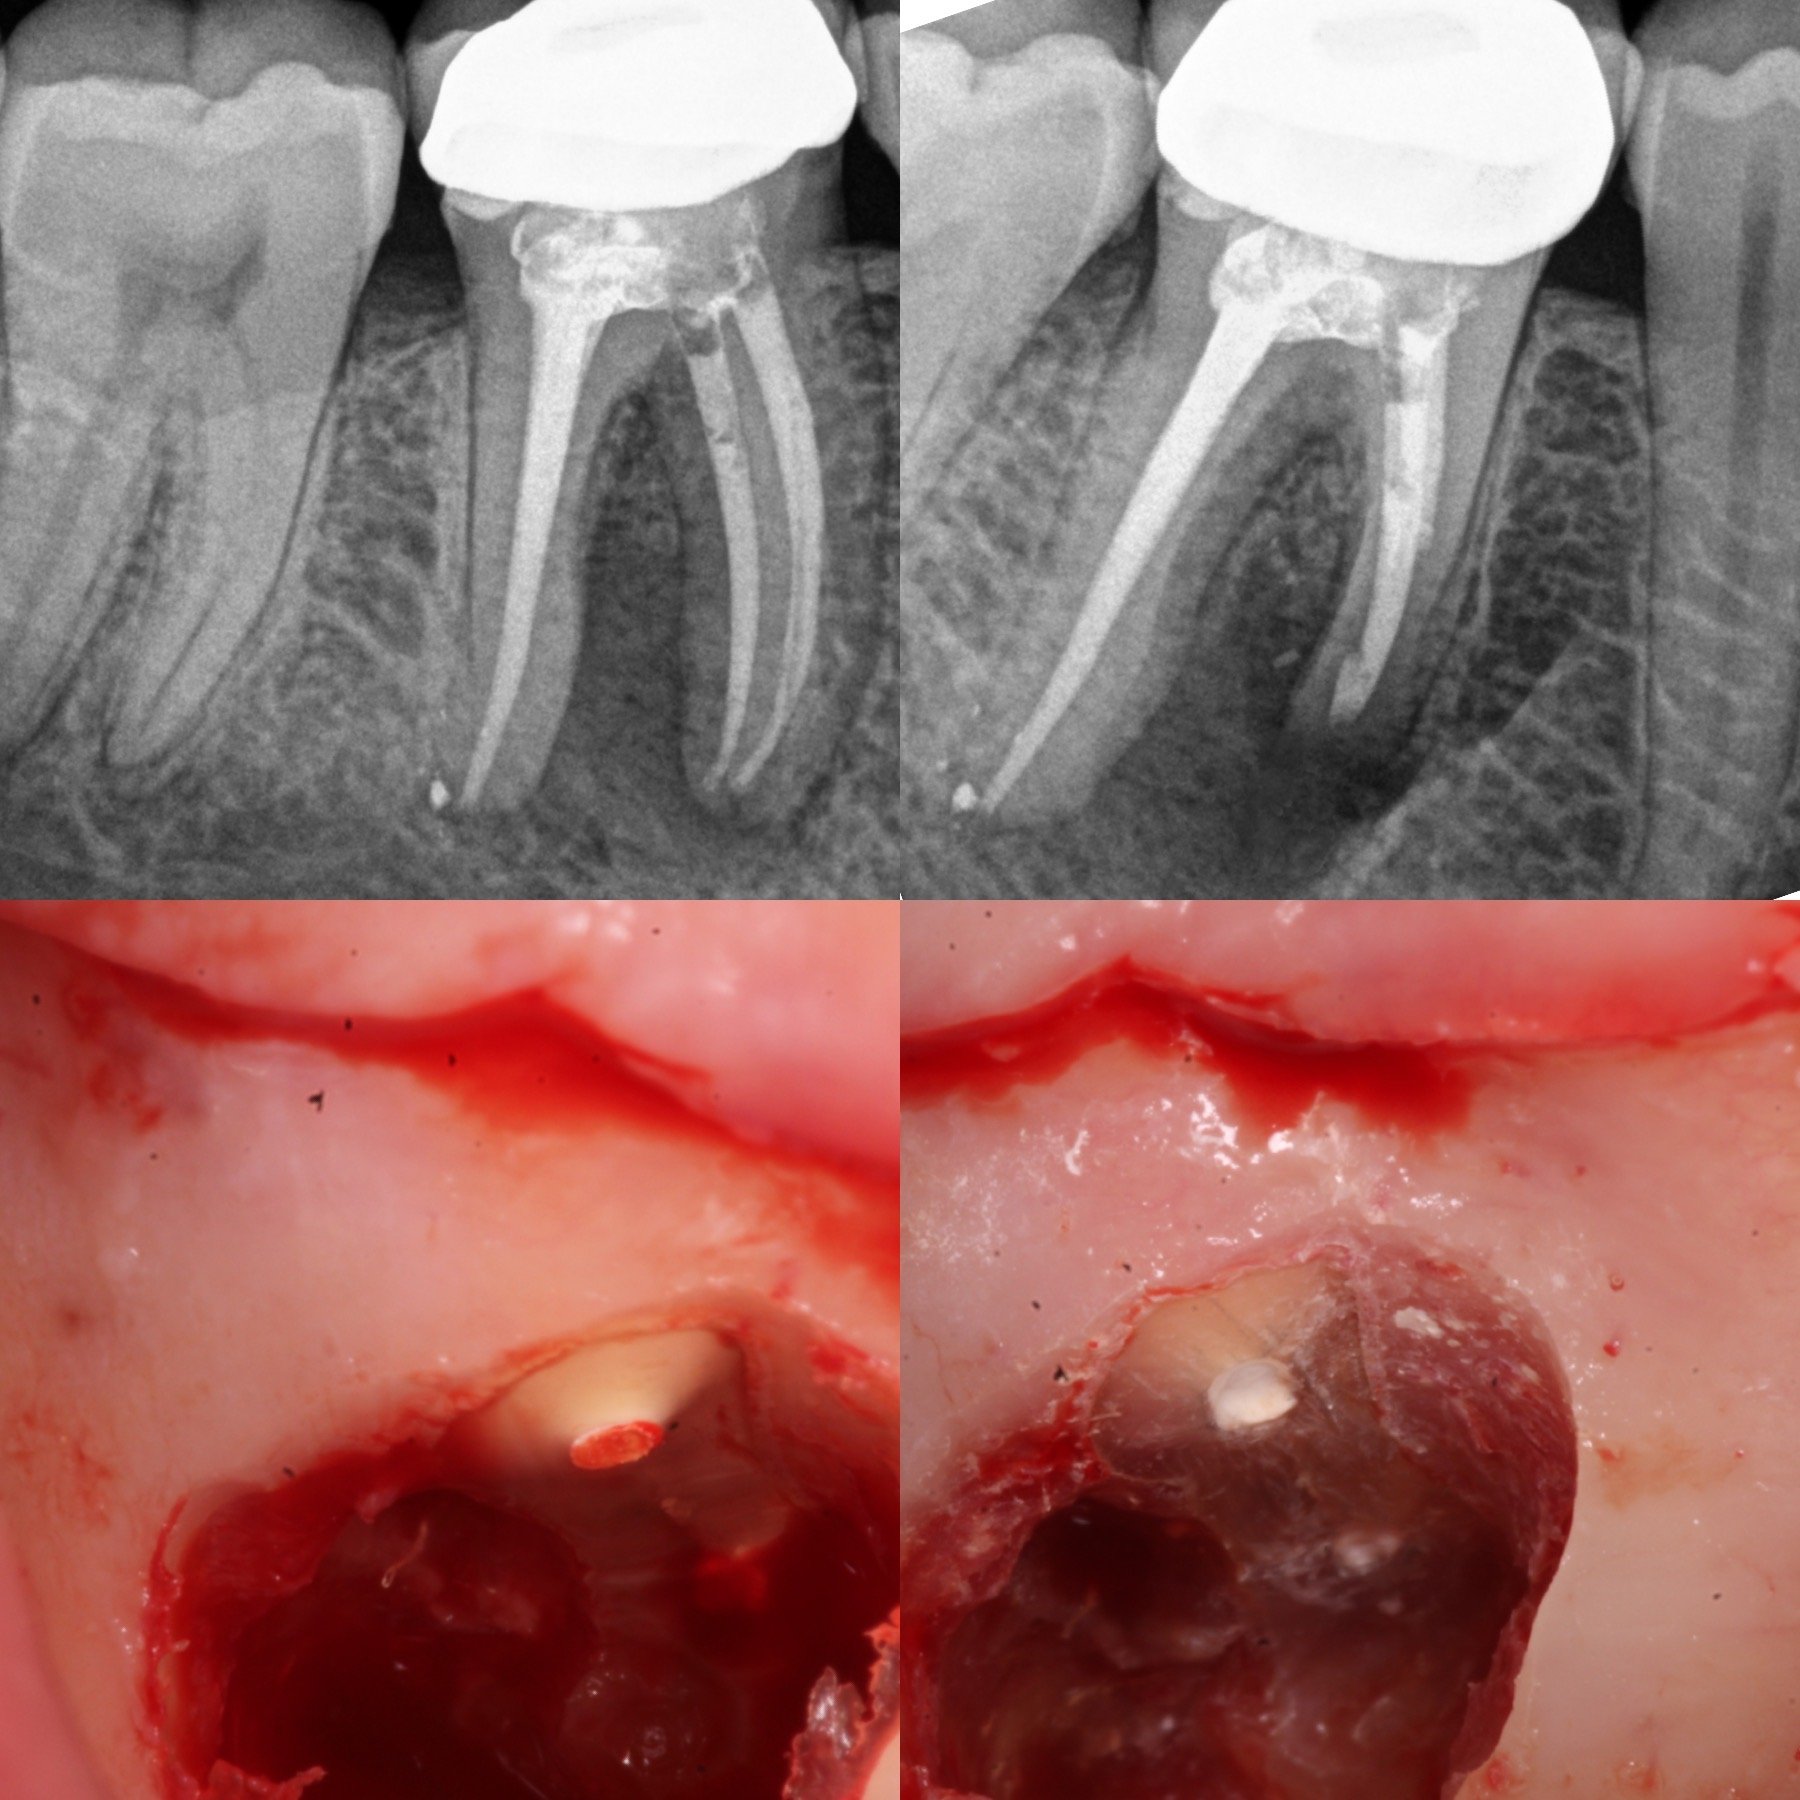

Microcirugía Endodontica

En ciertos casos, es necesario abordar problemas pulpares o infecciones mediante una microcirugía a través de la encía. Esta intervención permite tratar situaciones más complejas que podrían comprometer el pronóstico del diente.

La microcirugía endodóntica se realiza con técnicas mínimamente invasivas, lo que mejora la recuperación del paciente. Durante este procedimiento, se puede acceder a la raíz del diente afectado, permitiendo limpiar infecciones y sellar el diente.